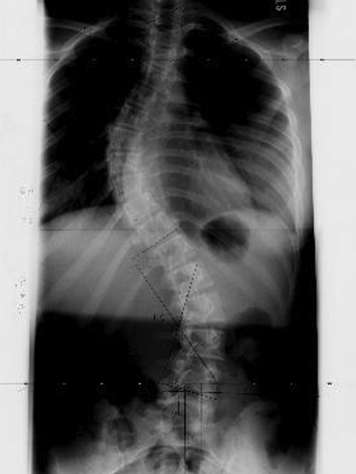

Un rayon X est un type de radiation qui passe à travers le corps. Il donne au chirurgien des renseignements sur la taille, la forme et l’emplacement des os de la colonne vertébrale. On l’appelle aussi radiographie. Les radiographies sont de loin l’outil diagnostique le plus fréquemment utilisé pour la scoliose. Elle en dit beaucoup au chirurgien, dont la plus importante, l’ampleur de la courbure de votre adolescent.

Plusieurs types de radiographies peuvent être faites :

- radiographie spinale postérieure-antérieure à trois pieds, c’est-à-dire une radiographie de la colonne de l’arrière vers l’avant.

- radiographie latérale à trois pieds, c'est- à dire prise sur le côté.

- Images en flexion, radiographie qui visent à tester la souplesse.

- radiographie pour déterminer l’âge des os, c’est-à-dire une radiographie de la main gauche qui vise à déterminer si votre adolescent grandit encore.

- radiographie pelvienne, c’est-à-dire une radiographie du pelvis pour déterminer si les os grandissent encore. On peut aussi faire des radiographies du coude pour déterminer la maturité des os.